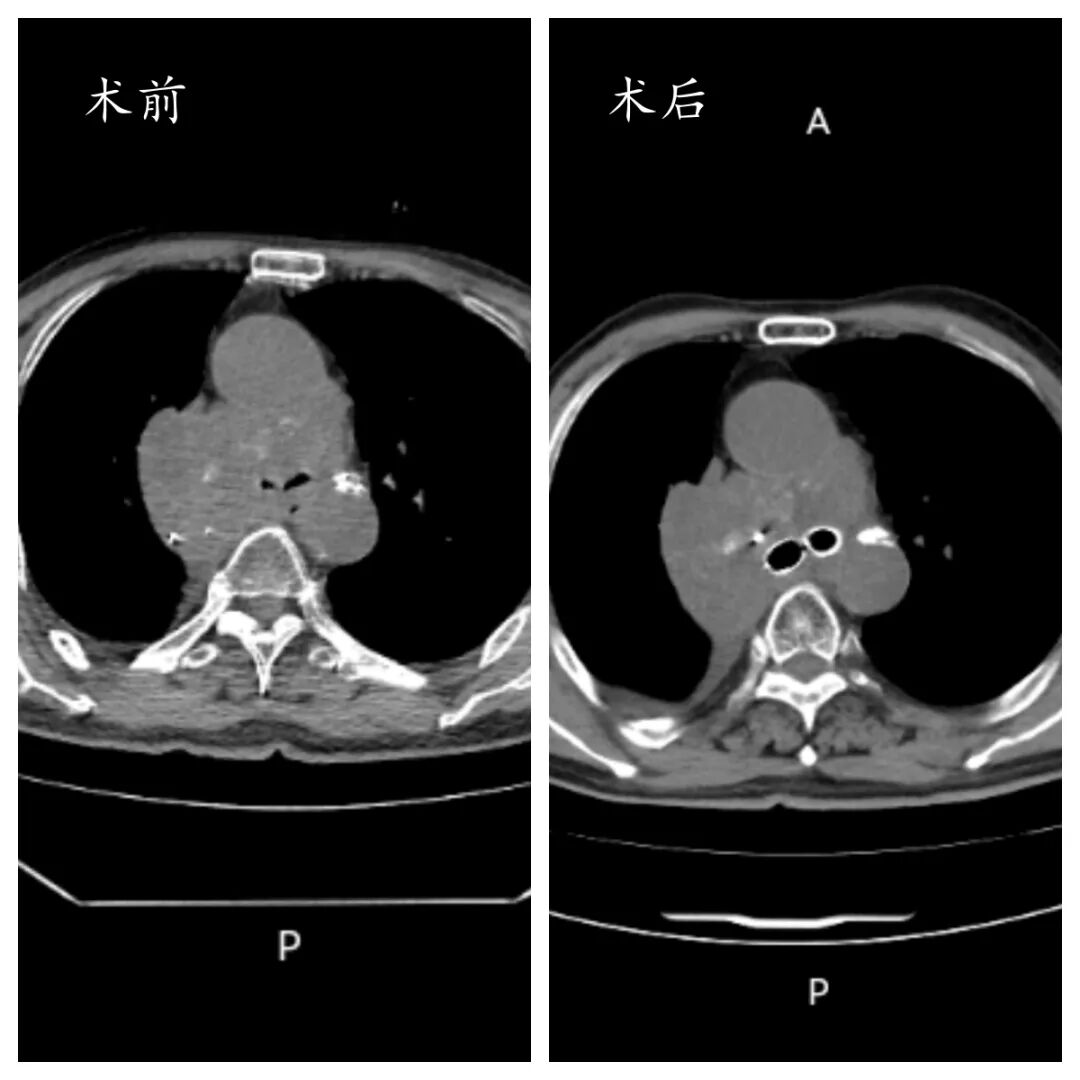

当肿瘤步步紧逼堵塞呼吸要道,当每一次吸气都成为奢望,一场与死神竞速的生死营救在我院手术室紧急上演。近日,临沂市中心医院呼吸与危重症医学科二病区介入团队凭借精湛医术,成功为一名肺癌致大气道严重梗阻患者独立实施高难度Y型支架置入术,精准打通“生命通道”,让患者重获呼吸希望。

患者秦先生(化名)因肺癌进展,出现进行性呼吸困难,病情急转直下,被紧急送往我院就诊。大气道作为人体呼吸的“核心主干道”,一旦被肿瘤严重堵塞,患者随时面临窒息风险。更为棘手的是,秦先生的肿瘤位置特殊,已累及气管隆突及双侧主支气管,形成复杂的气道梗阻,常规治疗手段难以奏效,生命危在旦夕。

经过数小时的攻坚克难,Y型支架成功精准置入,完全覆盖肿瘤狭窄段,双侧主支气管瞬间恢复通畅。当监测仪器上的血氧饱和度数值稳步回升,秦先生的呼吸逐渐平稳,整个手术团队终于松了一口气。

术后,秦先生的呼吸困难症状得到显著缓解,血氧饱和度恢复至正常水平,生命体征趋于平稳。在呼吸监护室接受两天的精细化治疗与护理后,患者病情稳定,生活质量大幅提升,顺利转回普通病房继续后续治疗。